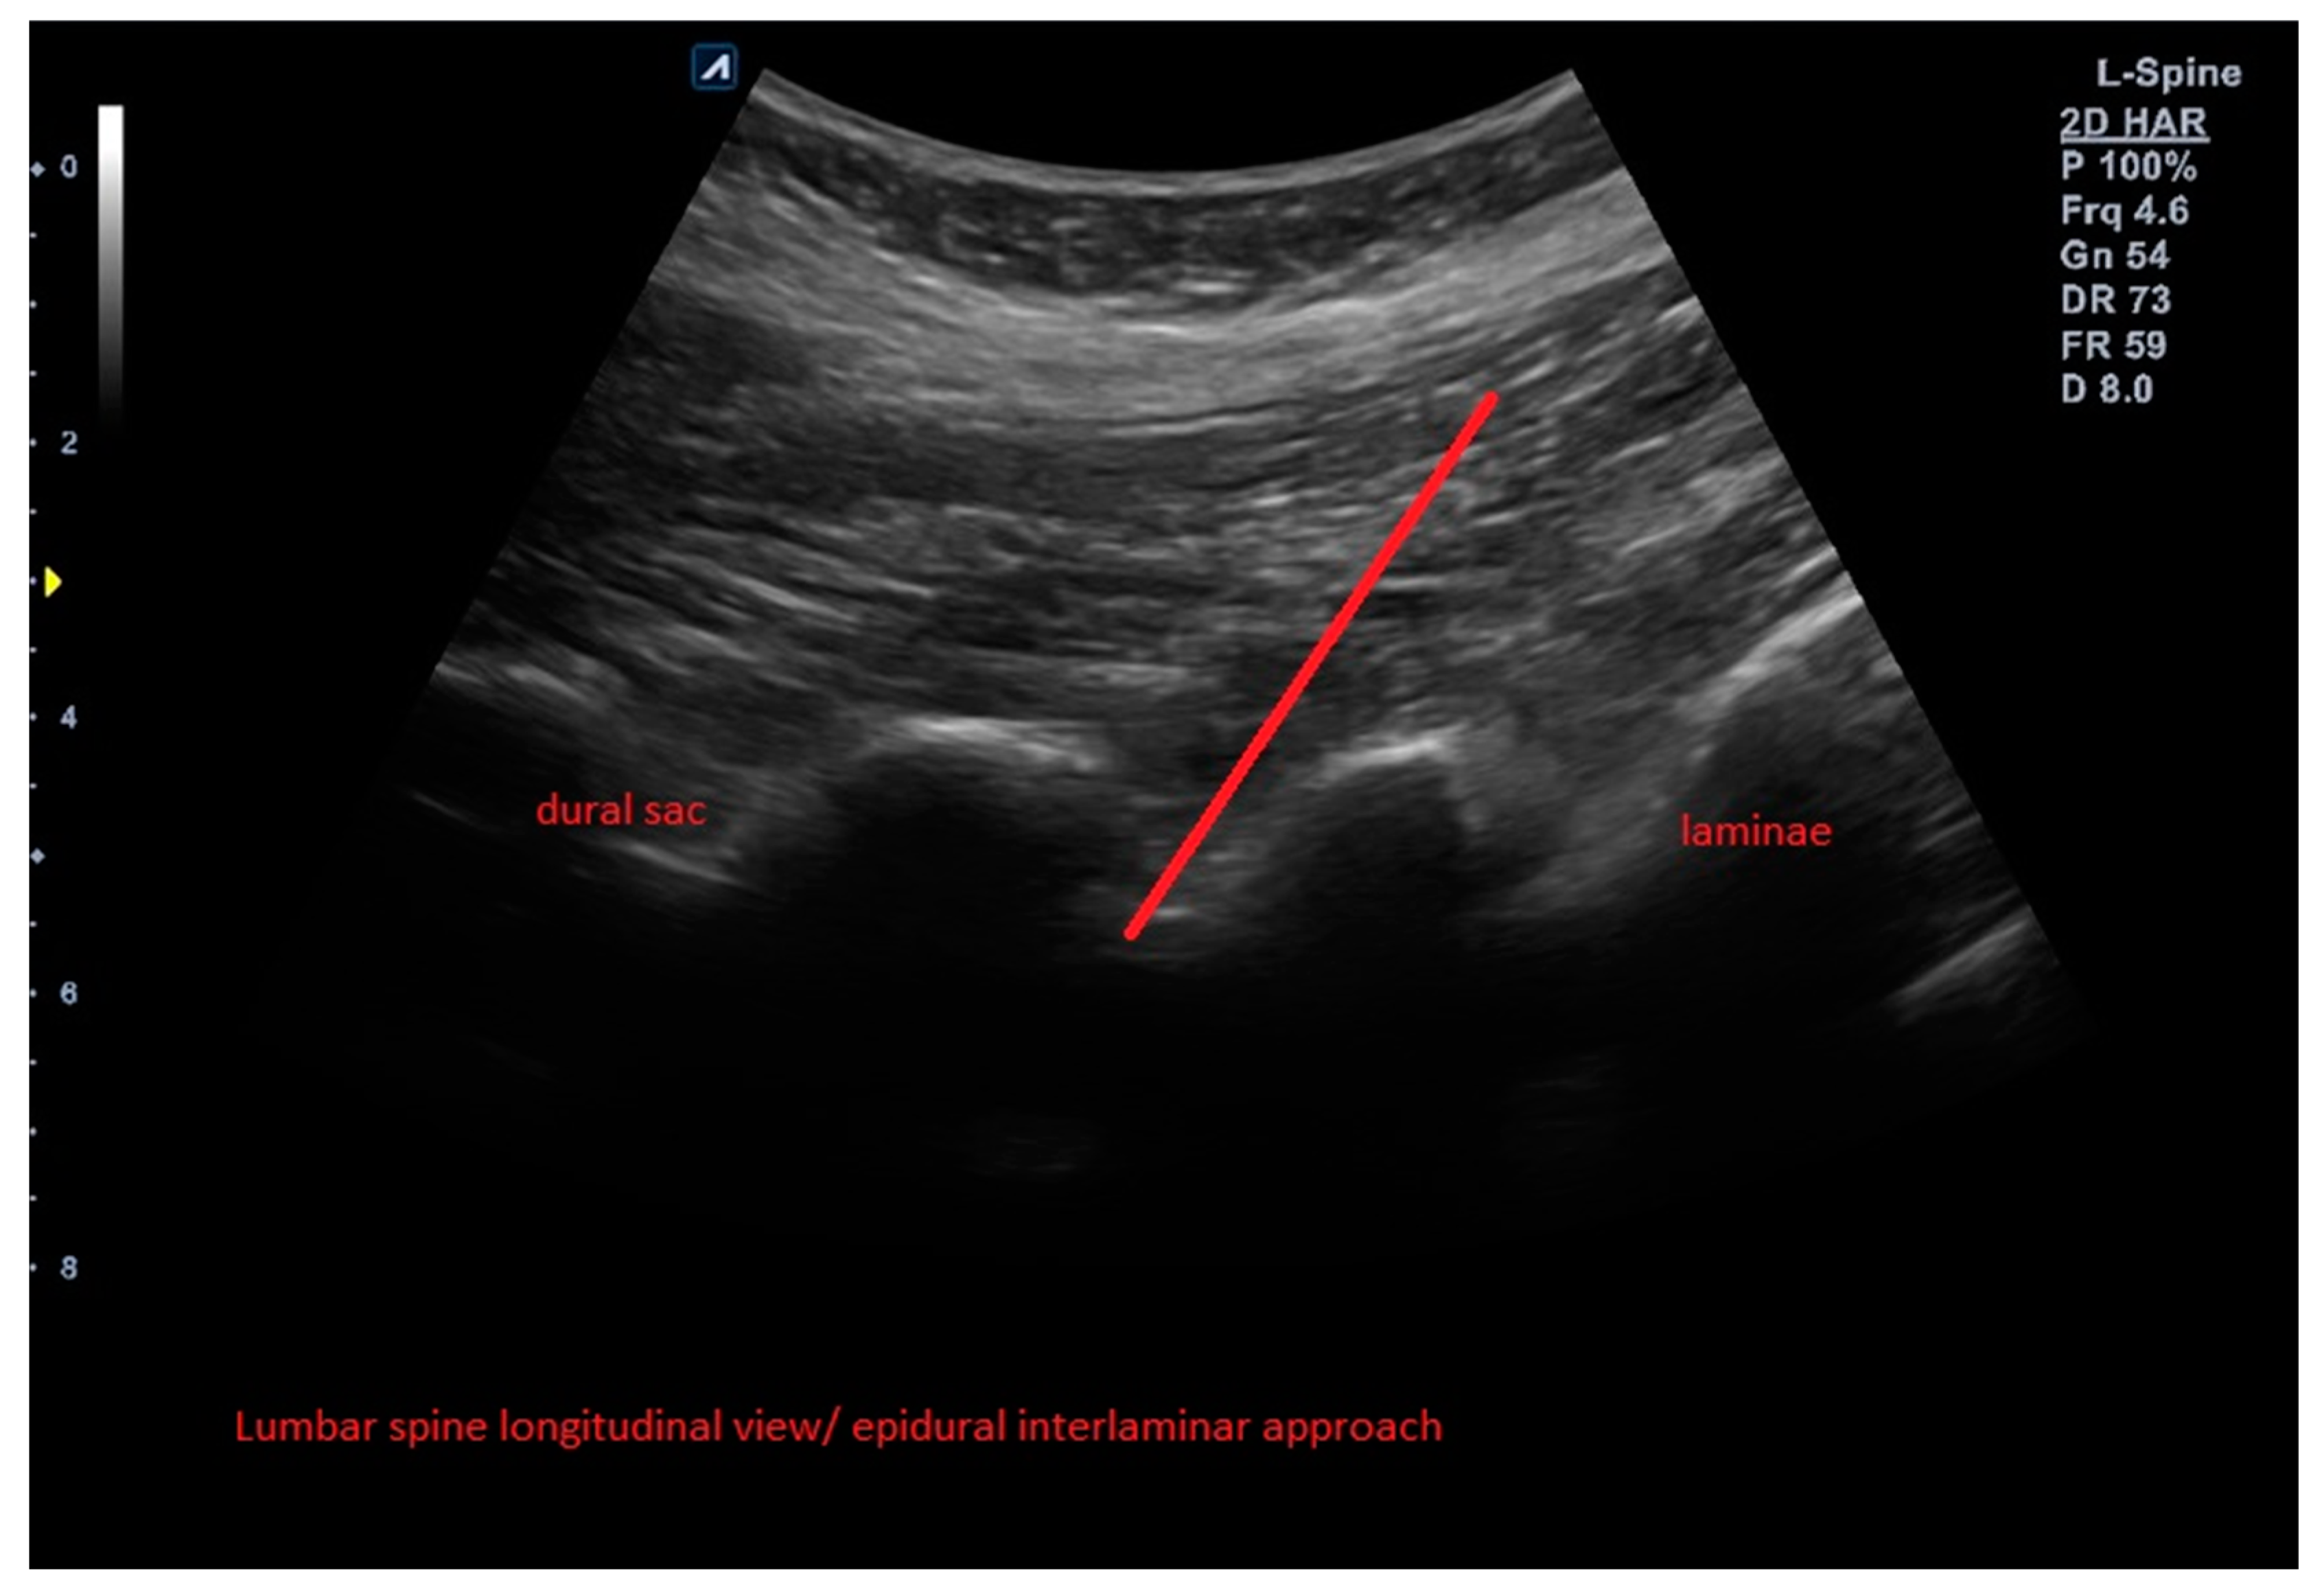

2.4. Interventions